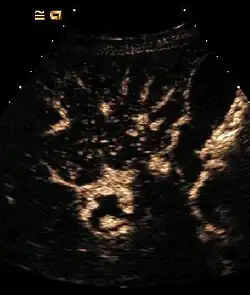

- Detektion und Charakterisierung von Lebertumoren: Das Muster und der Zeitpunkt der Kontrastmittelaufnahme von Veränderungen in der Leber macht in vielen Fällen eine genaue Artzuordnung möglich. Hier macht man sich eine Besonderheit der Leber zunutze. Im Gegensatz zu den meisten anderen Organen (Ausnahme Hypophyse) besitzt die Leber eine duale Blutversorgung: neben der Leberarterie wird das Organ über die Pfortader versorgt, welche nährstoffreiches Blut aus dem Darm zuführt. Spritzt man Kontrastmittel in eine Armvene, so wird dieses zuerst über die Arterien in die Leber gelangen (um dort u. a. die Gallenwege mit Sauerstoff zu versorgen), anschließend stellt sich das Kontrastmittel abfließend in den Lebervenen dar. Die Anflutung des Kontrastmittels in der Pfortader dauert am längsten (30–40 s), da das Blut erst im Darm zirkuliert und anschließend zur Leber gelangt. Lebereigenes Gewebe wird also auch in dieser sog. Spätphase Kontrastmittel enthalten. Metastasen leberfremder Tumoren enthalten natürlich kein Pfortadersystem und erscheinen daher kontrastmittelfrei (dunkel).

Manche Tumoren stellen sich im Kontrastmittelverstärkten Ultraschall so typisch dar, dass bei ihnen auf eine Leberbiopsie mittlerweile verzichtet wird.- Fokale noduläre Hyperplasie (FNH): Wird von einem Gefäßsystem mit Radspeichenmuster versorgt.

- Hämangiom: Aus dem zeitlichen Verlauf des Kontrastmittelanflutung von außen nach innen („Irisblenden-Phänomen“) wird auf ein Hämangiom geschlossen.